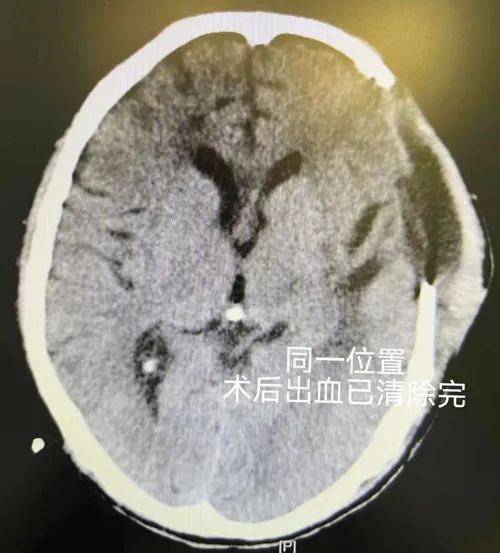

急查頭顱CT后

發(fā)現(xiàn)腦出血

且出血量大

清除顱內(nèi)出血

將老張顱內(nèi)血腫一點(diǎn)點(diǎn)清除

凌晨手術(shù)結(jié)束